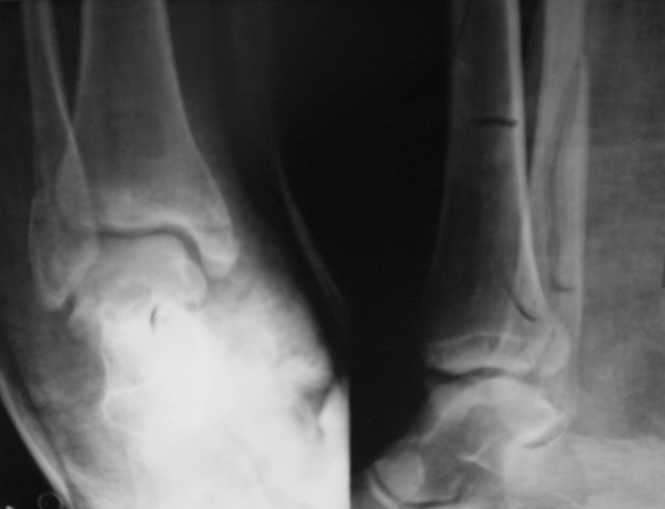

Перелом лодыжекКонтрольные рентгенограмы сделаны с нарушением укладок для стандартных проекций. Переделайте рентгенснимки и догда можно будет о чем-то иметь дискуcсию.

Рентгенограммы не сделаны в строго боковой и передне-задней проекциях.

Но и здесь видно, что внутренняя лодыжка "висит" - это говорит об интерпозиции. Выполняйте открытую репозицию и металлостеосинтез.

Укладка не точная, и тем не менее, медиальная лодыжка - сохраняется дислокация и соответственно интерпозиция. Остеосинтез мед. лодыжки, RTG контроль после этого - при отсутствии смещения латеральной - на этом можно остановиться ( межберцовый сендесмоз не поврежден ). Хотя это и не по AO. Успехов !

Стандартными снимками считается прямая, боковая и мортиз!!!, а так трудно гадать, насколько потеря длины малоберцовой. На боковом снимке не сопоставленный перелом медиальной лодыжки и перелом заднего края без смещения.

In this case we say about three malleolar fracture of ankle.Moreover lateral malleolus have external rotation displacement.Becouse this great suprise to me question - what kind of treatment.Of course open reduction with internal